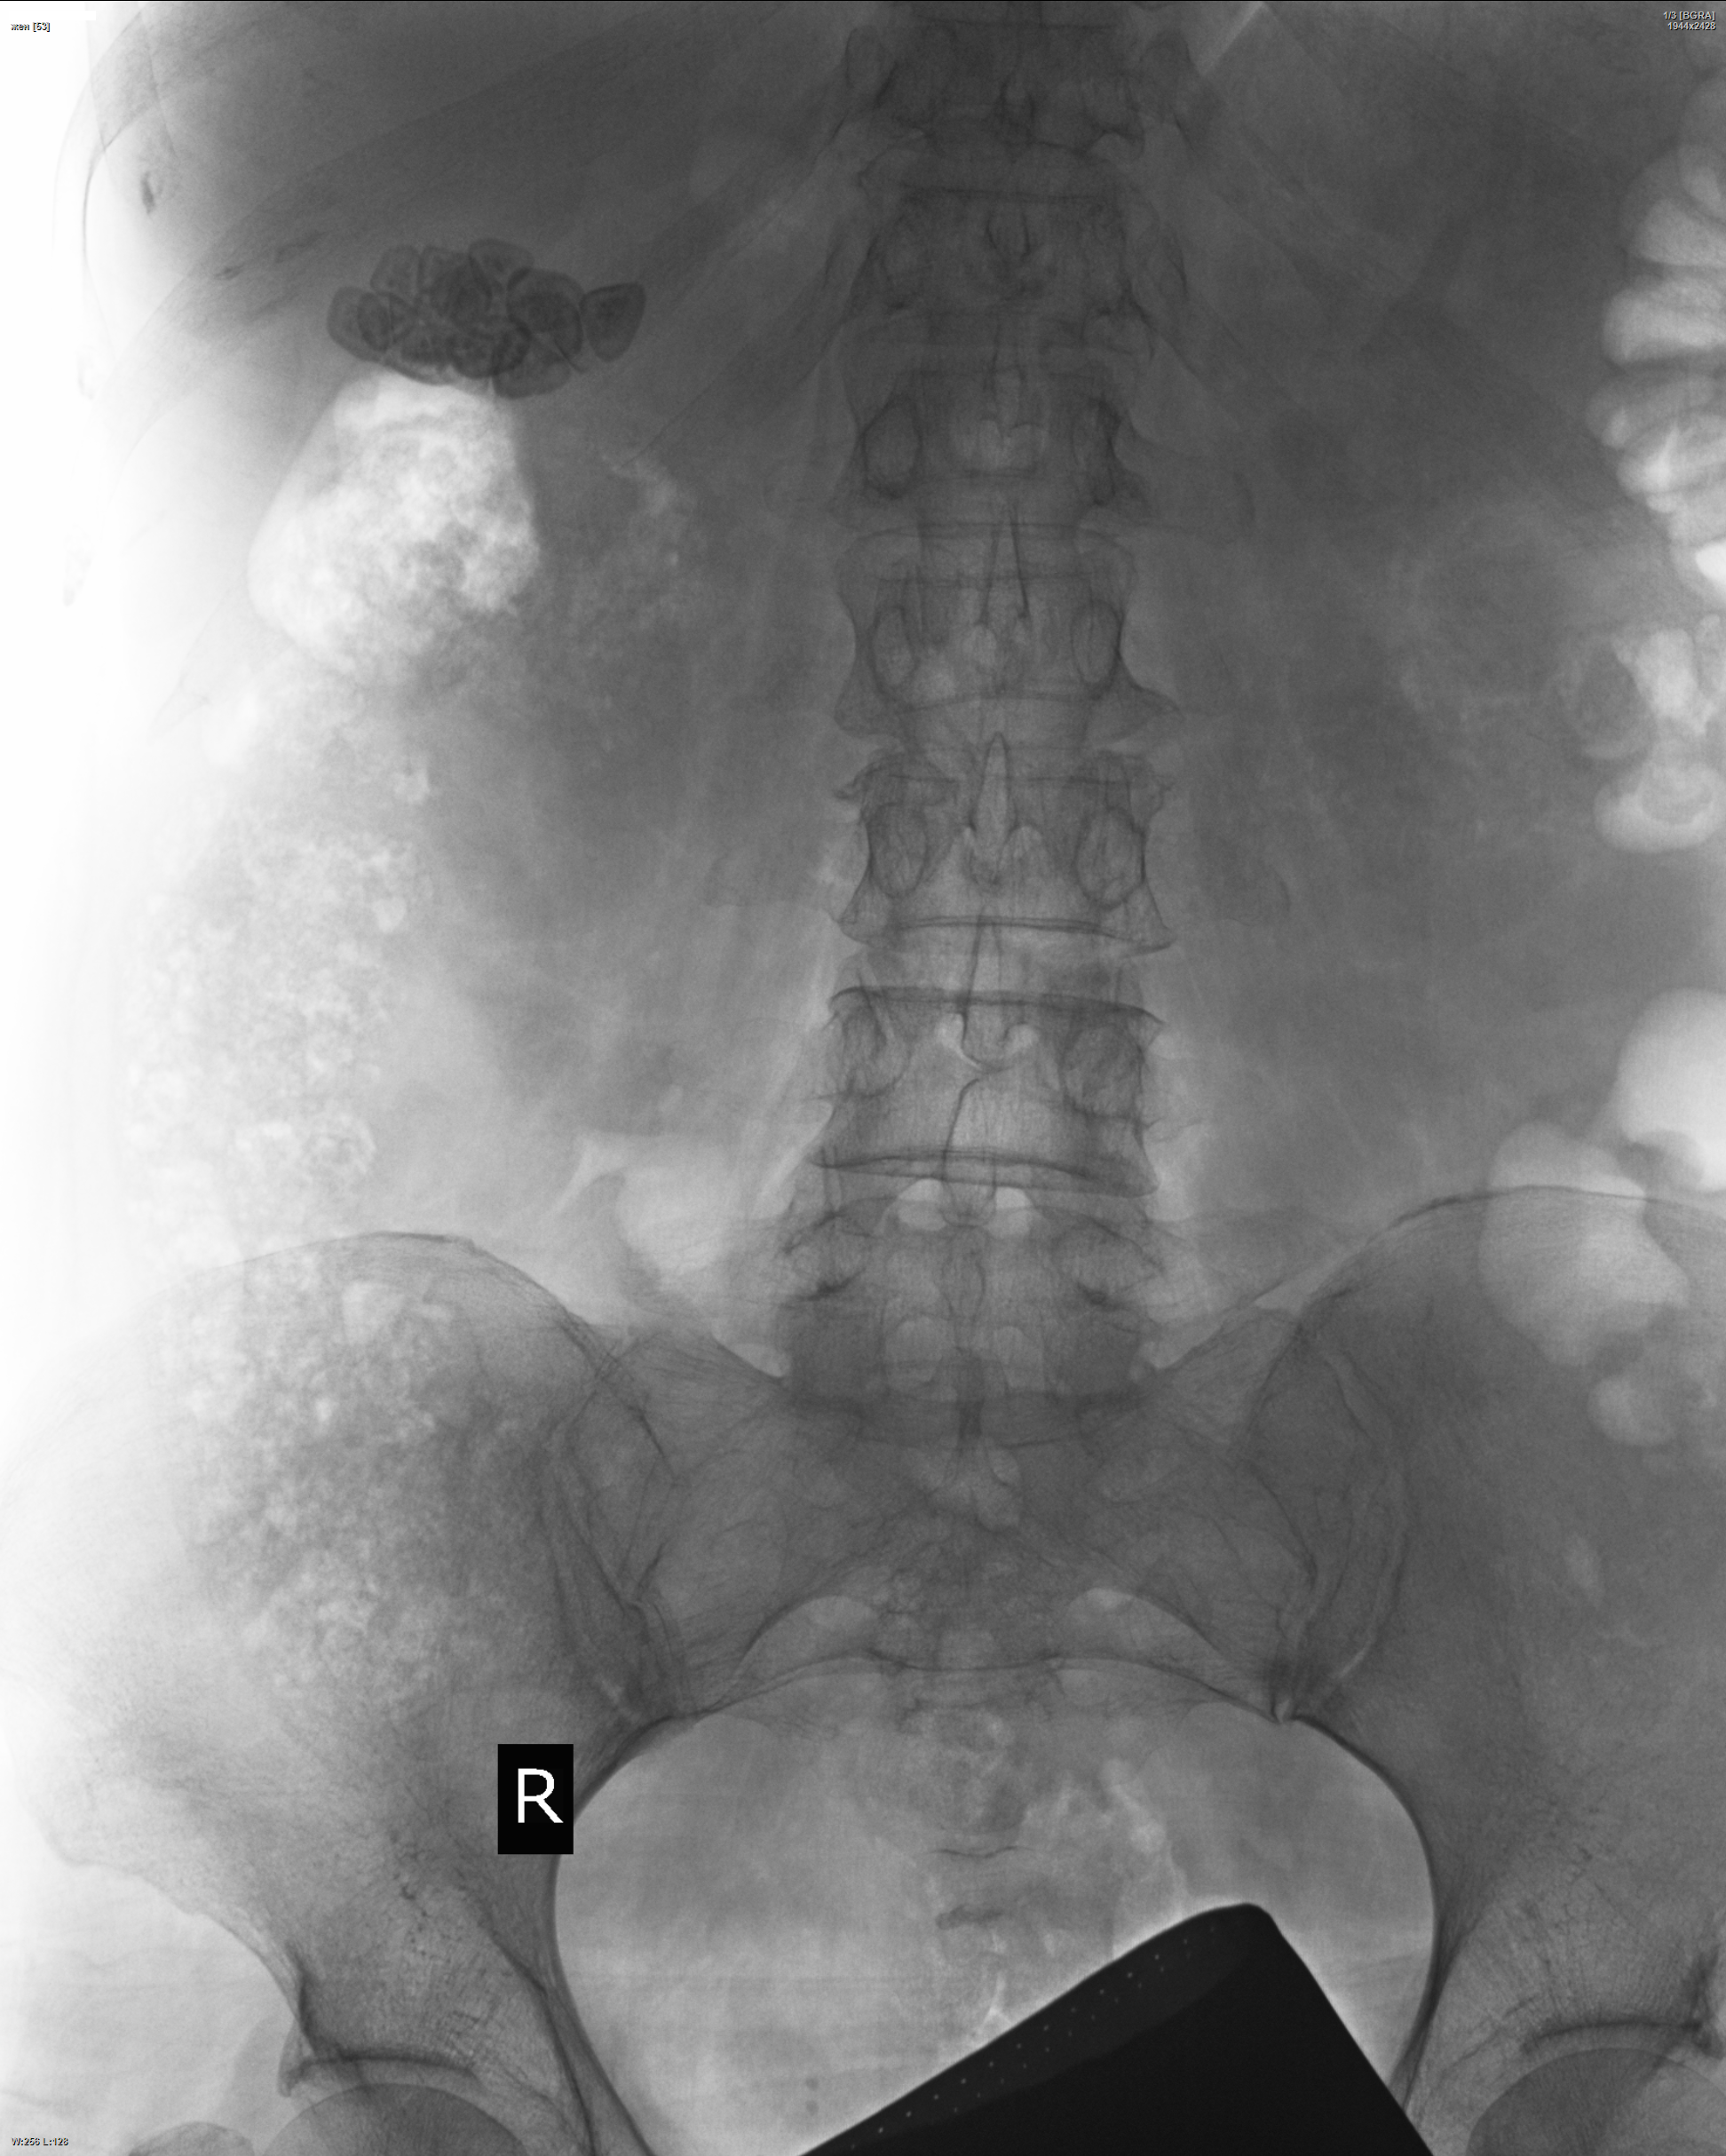

Всё своё, как говорится. Снимки получились на поясничный не очень, но на камешки - сгодится!) https://radiomed.ru/sites/default/files/styles/case_slider_image/public/user/19832/231_lst_0001.png?itok=9HjohUQ4 ID:47067 Пт, 18/04/2014 - 18:32 #1 maker4ik Не на сайте Был на сайте: 8 лет 6 месяцев назад Зарегистрирован: 19.10.2011 - 17:49 Публикации: 2682 По прямой прям как облачко! Пт, 18/04/2014 - 19:53 #2 И.Бондаренко Не на сайте Был на сайте: 3 дня 1 час назад Зарегистрирован: 13.09.2011 - 22:55 Публикации: 9206 Бриллианты. Сб, 19/04/2014 - 13:27 #3 Nobody Не на сайте Был на сайте: 11 лет 3 недели назад Зарегистрирован: 15.03.2014 - 20:29 Публикации: 2013 Мне ещё кишка с гаустрами нравится на боковой - листиком читается, слегка подъеденным гусеничкой.) "Лишь утратив всё до конца, мы обретаем свободу." F.C. Сб, 19/04/2014 - 16:59 #4 NIL Не на сайте Был на сайте: 3 часа 31 минут назад Зарегистрирован: 25.11.2013 - 20:50 Публикации: 18203 Nobody wrote: Мне ещё кишка с гаустрами нравится на боковой - листиком читается, слегка подъеденным гусеничкой.) А Вы - творческая натура! "Слушай всех, прислушивайся к немногим, решай сам".© Сб, 09/08/2014 - 14:59 #5 Nobody Не на сайте Был на сайте: 11 лет 3 недели назад Зарегистрирован: 15.03.2014 - 20:29 Публикации: 2013 В шапке весит снимок средних лет цыганки. А здесь снимок пожилой женщины, которая проработалавсю жизнь обычной дояркой...Приложения: "Лишь утратив всё до конца, мы обретаем свободу." F.C.

По прямой прям как облачко!

Бриллианты.

Мне ещё кишка с гаустрами нравится на боковой - листиком читается, слегка подъеденным гусеничкой.)

В шапке весит снимок средних лет цыганки. А здесь снимок пожилой женщины, которая проработалавсю жизнь обычной дояркой...